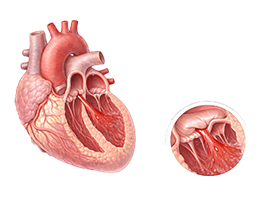

심근경색 (Myocardial Infarction)

협심증 (Angina Pectoris)

심근병증 (Cardiomyopathy)

심장판막질환 (Valvular Heart Disease)

심부전 (Heart Failure)

비대성심근병증 (Hypertrophic Cardiomyopathy)

확장성심근병증 (Dilated Cardiomyopathy)

울혈성심부전 (Congestive Heart Failure)

심근염 (Myocarditis)

심막염 (Pericarditis)

심내막염 (Endocarditis)

심정지 (Cardiac Arrest)

돌연심장사 (Sudden Cardiac Death)

심방세동 (Atrial Fibrillation)

심실빈맥 (Ventricular Tachycardia)

심실세동 (Ventricular Fibrillation)

서맥 (Bradycardia)

심장판막질환 (Heart Valve Disease)

폐동맥고혈압 (Pulmonary Hypertension)

심장병성쇼크 (Cardiogenic Shock)

심장막압전 (Cardiac Tamponade)

확장형심근병증 (Dilated cardiomyopathy)

비후성심근병증 (Hypertrophic cardiomyopathy)

제한성심근병증 (Restrictive cardiomyopathy)

감염성심내막염 (Infective endocarditis)